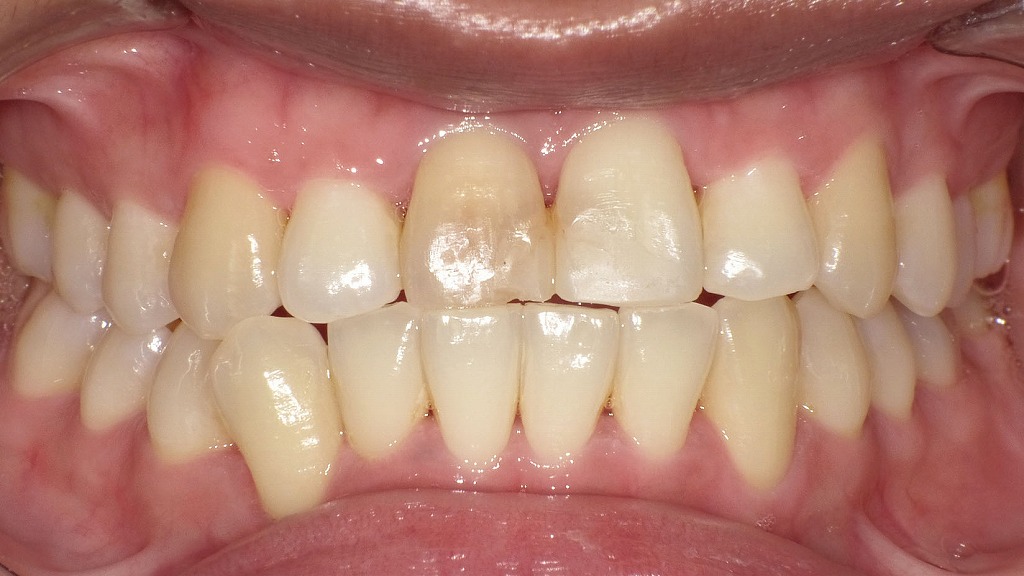

歯がむずむずする原因は初期虫歯?プラークが引き起こす最初のサイン

画像では、矢印の部位に以下のような初期虫歯(脱灰)と歯肉炎の兆候が確認できます。

● 白濁した部分(ホワイトスポット)

赤矢印で示す歯の表面には、白く濁った部分=エナメル質の脱灰が見られます。

これは虫歯の最初のステージで、

- 痛みはまだない

- しみる・ムズムズする

- 表面はまだ穴になっていない

という“初期虫歯”の典型的な所見です。

● プラーク(黄色い付着物)

歯の縁(特に犬歯・小臼歯付近)に黄色いプラークが広範囲に付着しています。

このプラークの中の細菌が酸を作り、エナメル質を溶かすことで初期虫歯が進行します。

【なぜ“むずむず”する?】

初期虫歯では、エナメル質の表面が溶け始めると内部の象牙質に刺激が伝わりやすくなり、

- ムズムズする

- 違和感がある

- 触りたくなる感覚がある

といった軽い知覚症状が出ます。

穴があく前の段階なので、フッ素・歯磨き指導・プラーク除去で回復可能なのが特徴です。